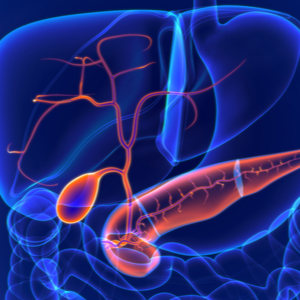

Aizkuņģa dziedzera vēzis

Žultspūšļa karcinoma

Holangiokarcinoma - Žultsceļu karcinoma